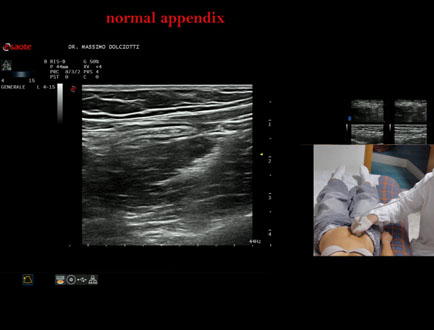

Data inserimento: 01/08/2025

Ecografia del: 11/07/2025

Strumento: Esaote MyLab Eight

Sonda: Lineare Multifrequenza 4-15 MHz

Età Paziente: M 12 anni

Motivazione dell'esame: recente infezione virus mononucleosi infettiva

Commento all'esame: le immagini ed il video documentano l'appendice di calibro regolare (4,8-5,2 mm - v.n. < 6 mm).

Conclusioni: appendice normale (normal appendix).

Presentazione: Dr. Massimo Dolciotti - Ancona